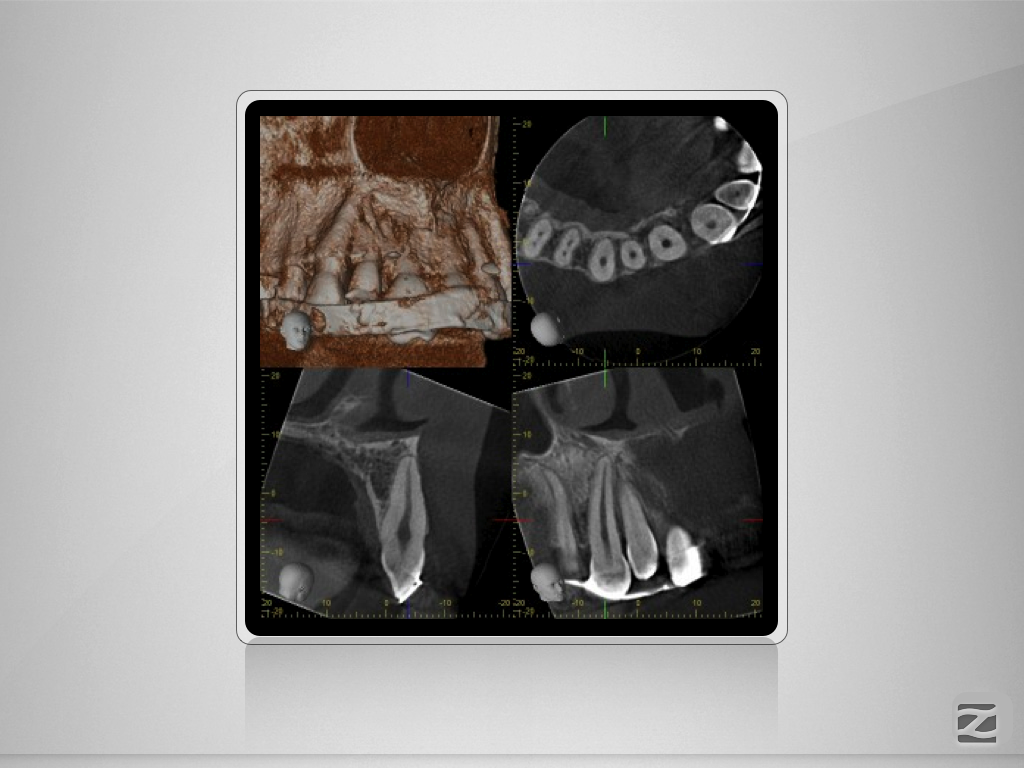

Multitrauma D.010

Mehrfach-Trauma